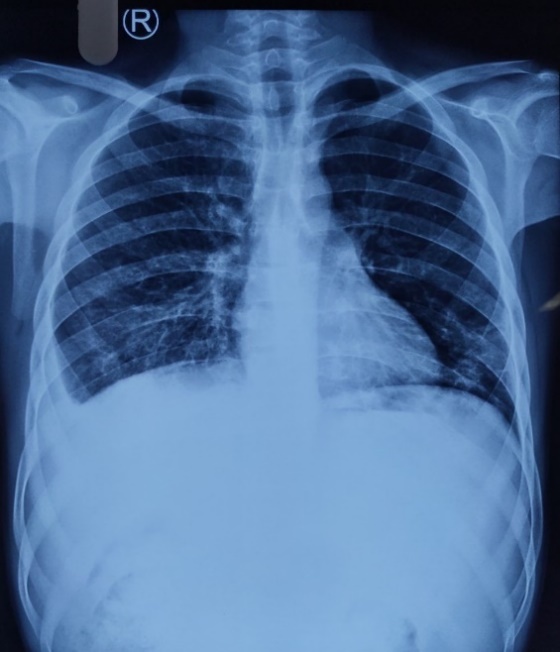

How To Differentiate Pleural Effusion And Consolidation . In general, an exudative effusion meets at least one light’s. This is also called cardiogenic edema, to. Thoracic ultrasound (also known as lung ultrasound [lus]) is increasingly being used to guide patient management. Thoracentesis is commonly used to differentiate transudative versus exudative effusions. Pleural effusions are abnormal accumulations of fluid within the pleural space. To further characterise pleural effusion and investigate for an underlying cause. What’s the difference between lung consolidation and pleural effusion? A pleural effusion describes an excess of fluid in the pleural cavity, usually resulting from an imbalance in the normal rate of pleural fluid production or absorption, or both. Look for consolidation (infection), malignancy, cardiomegaly (cardiac failure) and pleural plaques (asbestos exposure). The most common cause of diffuse consolidation is pulmonary edema due to heart failure. Other relevant imaging investigations include: Pleural effusion is the buildup of fluid between the chest cavity and the tissue lining the lungs. They may result from a variety of pathological.